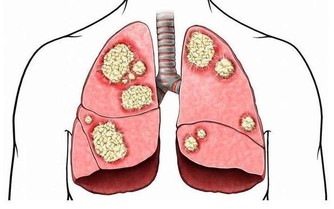

安眠藥能使呼吸減弱,降低心跳,緩解神經,而酒精本身也能抑制呼吸和心跳,兩者在一起會使抑製作用翻倍。會使人思維緩慢、思維遲鈍,還會導致昏睡不醒,甚至會導致呼吸減弱使血壓嚴重下降,從而造成呼吸停止,最後一條人命沒了。